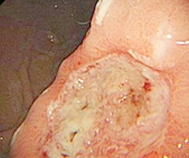

医生简介:副主任医师,王浩波凭借其在消化内科领域的杰出贡献,多次受邀出席全国重要学术会议、论坛。为广大患者解除口臭困扰。对急慢性胃炎、反流性食管炎、消化性溃疡等常见疾病具有丰富的诊疗经验...【详细】

医生简介:从事消化系统疾病临床工作30余年,具有丰富的临床经验,深厚的专业理论基础和较强的科研能力。多次在湖北中医学院进修学习,擅于运用中西结合的方法,对各种消化疾病进行有效诊疗...【详细】

医生简介: 主治医师,从事消化内科临床诊疗工作30余年,具有丰富的临床诊疗经验,对西医治疗消化系统胃肠疾病的诊断及治疗有独特见解。擅长西医治疗各种常见胃肠道疾病,对胃肠疑难杂症的治疗...【详细】

医生简介: 从事消化内科临床工作40余年 擅长诊治口臭,反流性食管炎,慢性胃炎,胃十二指肠溃疡,萎缩性胃炎,胃息肉,腹泻、便秘、溃疡性结肠炎,慢性结肠炎,肠息肉...【详细】